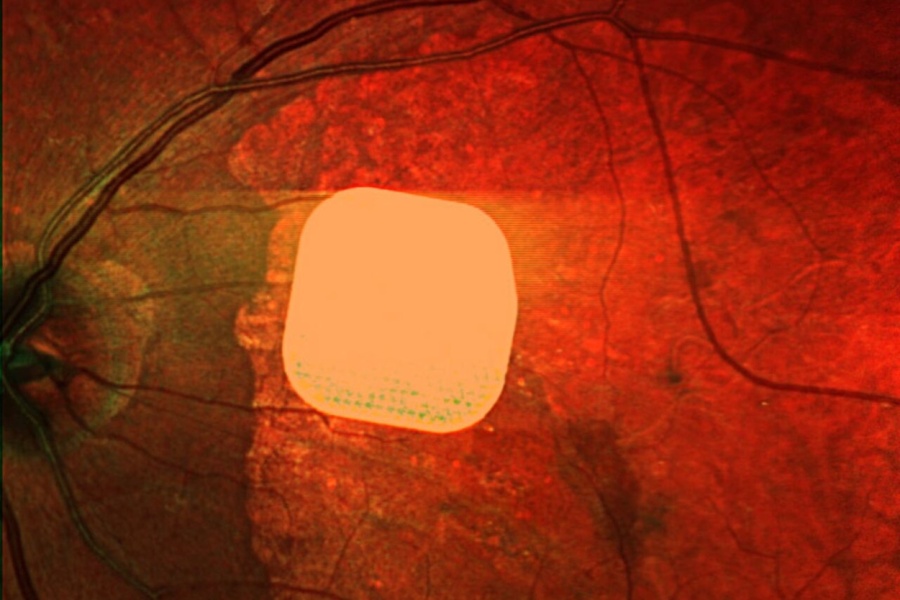

یک ایمپلنت الکترونیکی به ضخامت نصف موی انسان، بینایی را به بیماران مبتلا به نابینایی غیرقابل درمان بازگردانده است. این دستاورد میتواند آغازگر عصر جدیدی در مبارزه با نابینایی باشد.

مشخصات فنی ایمپلنت

ابعاد: ۲ در ۲ میلیمتر (بسیار نازک)؛

نام دستگاه: پریما/ Prima؛

روش کاشت: جراحی ویترکتومی در کمتر از دو ساعت.